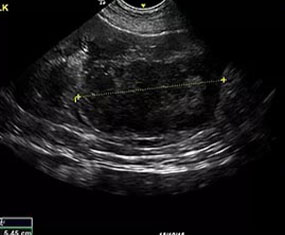

At RVUS we have chosen industry leading equipment from vendors with reputable and proven track records in the industry. From the front lines to your final report it is imperative that the equipment and the user provide images that equip the specialists with the highest level of quality and reproducibility to confidently provide an accurate interpretation of the sonogram.

This, in turn, provides you with additional tools to arrive at a diagnosis and prognosis and to enhance the care model for your patient and confidence with your client. Our team of professionals with decades of ultrasound experience encourage the use of ultrasound as a leading route to non-invasively assess organs and pathology in question. To cover that spectrum, a variety of transducers are essential, all with different characteristics.

Whether your patient is 100 lbs or 10 lbs, take comfort in knowing your sonographer is capable of generating images that are sensitive and specific to the clinical concerns.